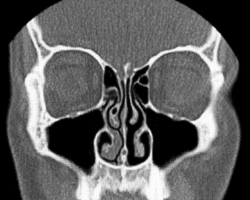

Normal Nose CT Front cross section -